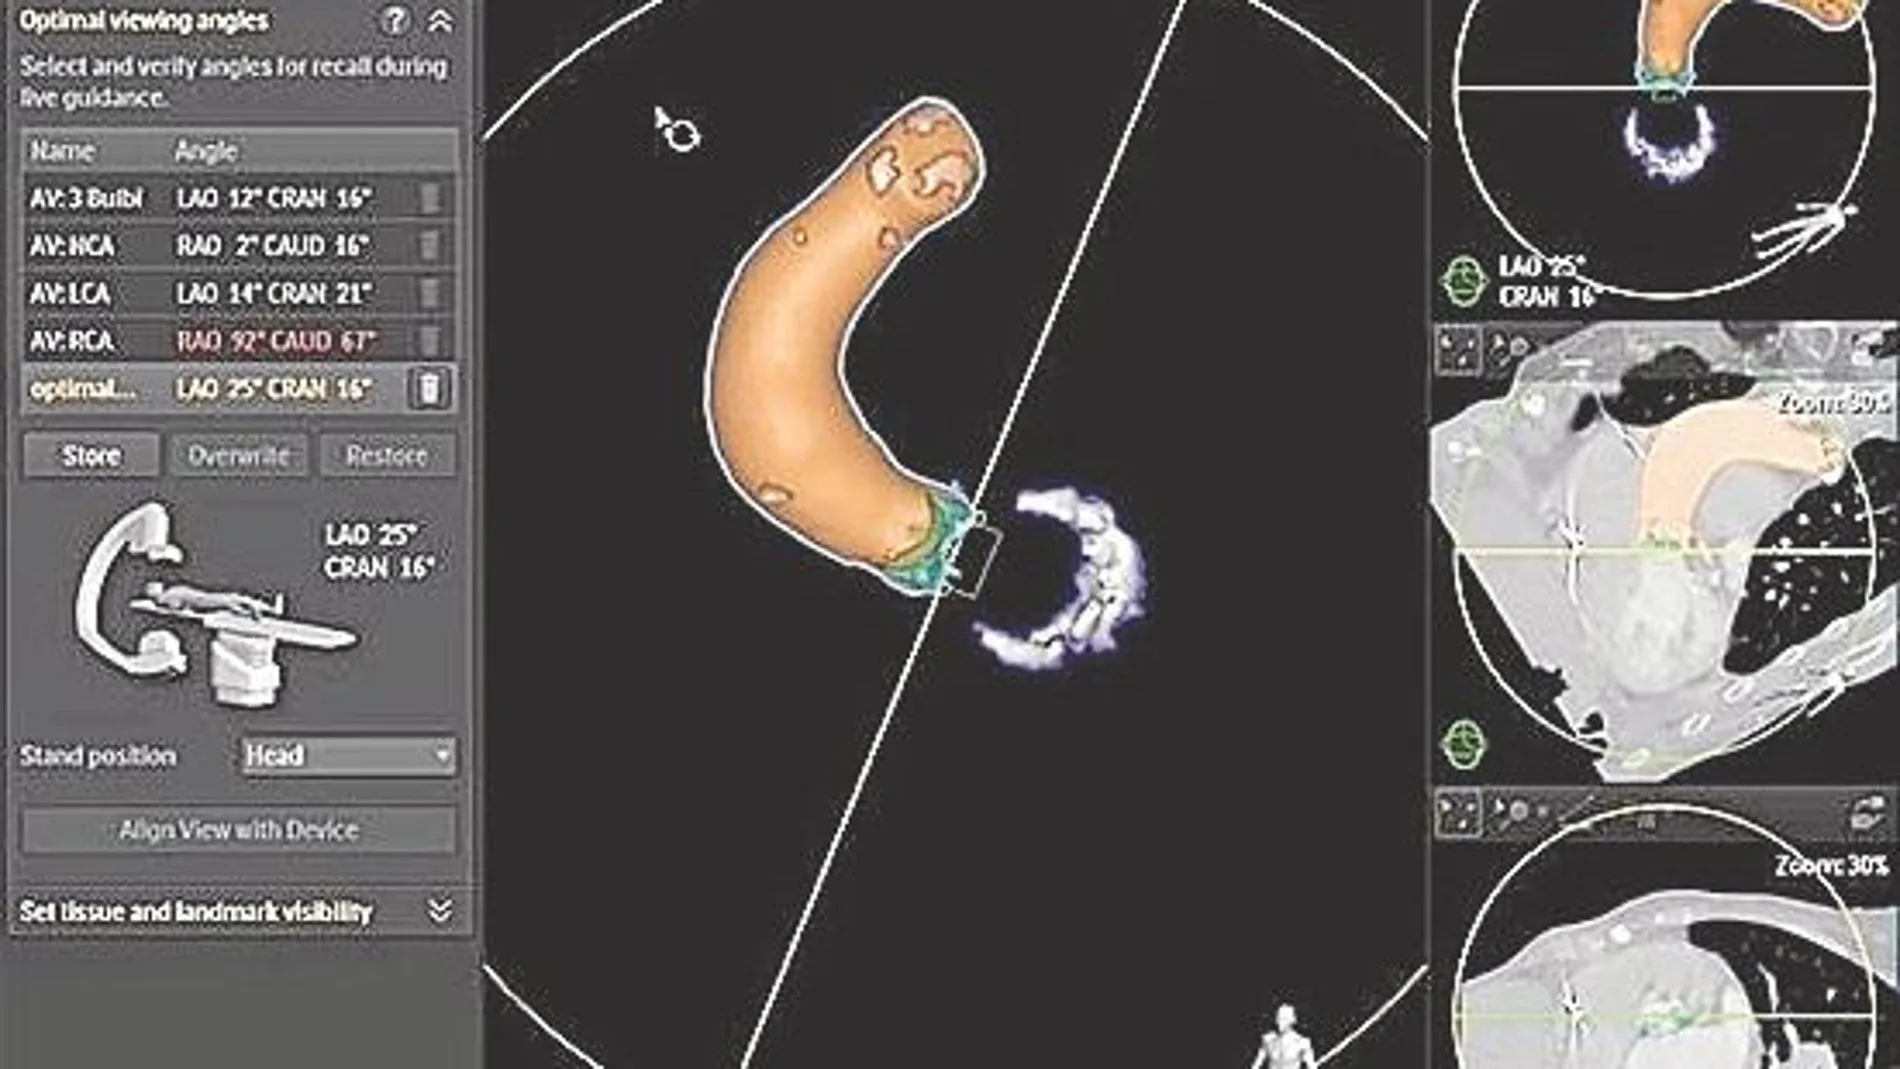

Suponen un desafío para el profesional, ya que además, las nuevas y complejas intervenciones en cardiopatías estructurales requieren que los especialistas trabajen conjuntamente, guiados con rayos X y ecografías para visualizar las zonas anatómicas esenciales, por donde navegan los cateteres. Ya sea para implantación de válvula aórtica transcatéter (TAVI), clipado de la válvula mitral u oclusión de la orejuela izquierda, las imágenes 3D mejoran la identificación de los objetivos, simplifican la implantación de dispositivos y posibilitan una evaluación inmediata de los resultados.

En la actualidad, se han desarrollado herramientas de inteligencia anatómica para planificar y tratar enfermedades cardiacas. Hay herramientas que superponen la imagen del escáner CT con la de Rayos X en tiempo real y realizan una medición automática de las características anatómicas individuales del corazón de cada paciente. De esta manera, el clínico puede conocer el diámetro exacto de la válvula aórtica, u obtener el perímetro, y verlo representado en una imagen en 3D señalada por un código de colores que distingue las estructuras. Esto permite segmentar el músculo cardiaco y visualizar únicamente la estructura anatómica sobre la que el médico va a trabajar, desde cualquier ángulo (360º). Las herramientas para intervenciones específicas y la integración de modalidades de diagnóstico por imagen multiplican la fiabilidad y mejoran el flujo de trabajo del equipo de cardiología.